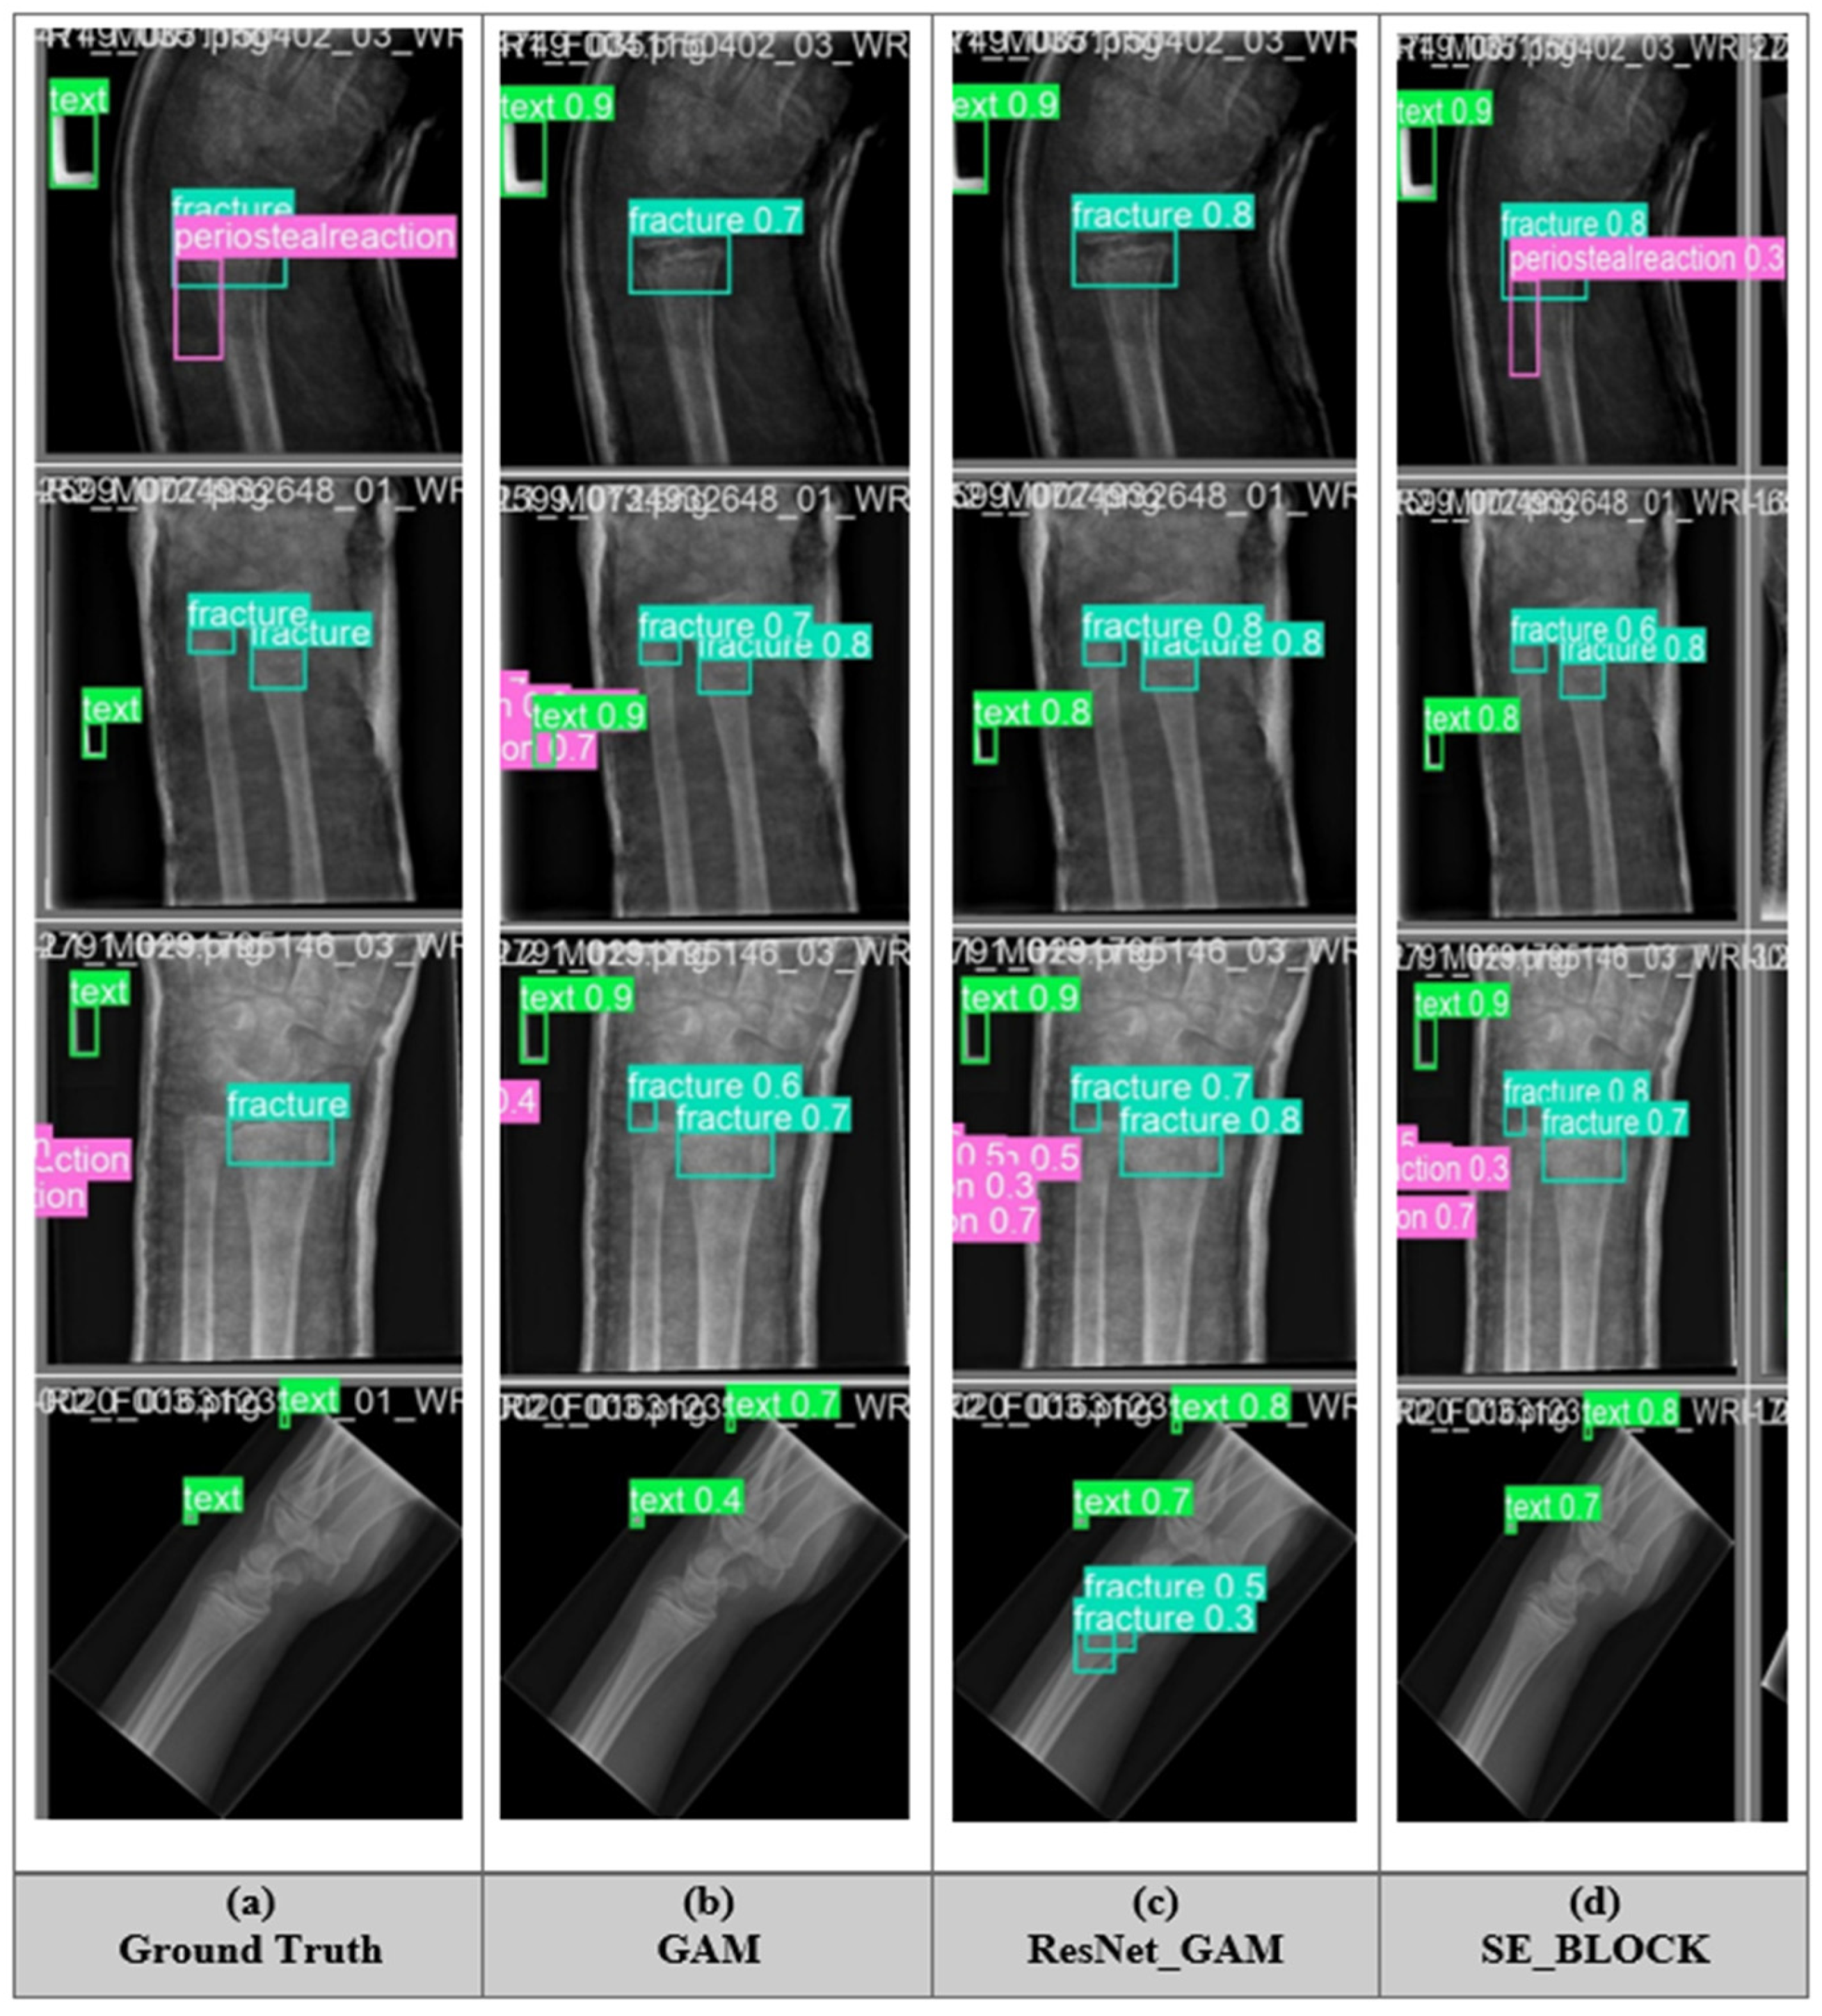

5.5. Fracture Detection of All Model

5.9. Application